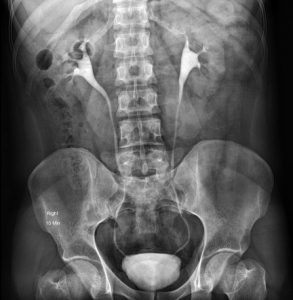

پیلوگرام داخل وریدی (IVP یا Intravenous pyelogram)

پیلوگرام داخل وریدی (IVP) که اوروگرام داخل وریدی (IVU یا intravenous urogram) نیز نامیده میشود، یک عکس اشعه ایکس از تمام سیستم ادراری است که پس از تزریق یک رنگ مخصوص به ورید، گرفته میشود. این رنگ توسط کلیهها از جریان خون خارج شده و سپس وارد حالبها و مثانه میشود. در حالی که این اتفاق در حال وقوع است، اشعه ایکس انجام میشود. رنگ، این اندامها را در اشعه ایکس مشخص میکند و به نشان دادن تومورهای دستگاه ادراری کمک میکند.

مهم است که اگر آلرژی دارید یا تا به حال به رنگهای اشعه ایکس واکنش نشان داده اید یا هر نوع مشکل کلیوی دارید، به پزشک خود اطلاع دهید. اگر چنین است، ممکن است پزشک شما آزمایش دیگری را به جای آن انجام دهد.